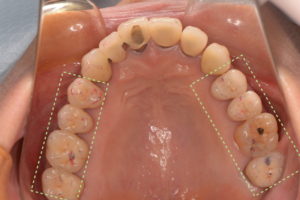

治療方法 厚み30μmの噛み合わせチェック用の咬合紙と、厚みが8μmのオクルーザルレジストレーションストリップスというものを用いながら他の歯よりも強く当たっている歯を見つけます(緑の点線で囲んだところ)。

その部位を細かく調整します。 治療には数回の通院を要しますが、毎回、左右で4〜5本ずつの歯がバランスよく当たるように調整していきます。